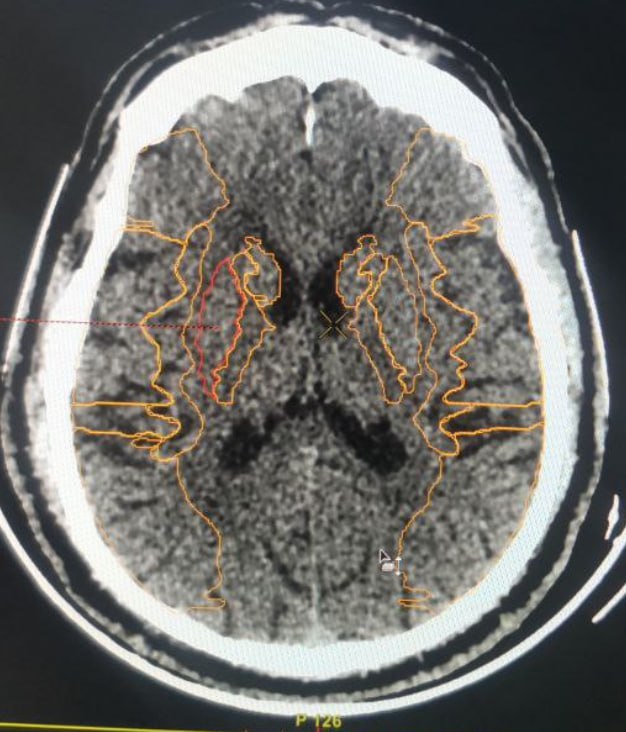

КТ на момент поступления и МРТ при ухудшении состояния через два дня.

Лаборант, по одной, ему лишь ведомой, причине, сделал МРТ фронтальными сканами, пришлось из фронтального сделать аксиальный, для лучшей сравнимости.

Интересно, что ИИ насчитал 9 баллов по ASPECTS, а глазом вообще ничего не видно было.

Тромболитическая терапия не проводилась из-за противопоказаний, через двое суток произошла спонтанная геморрагическая трансформация и инфаркт, как выяснилось, был не 9, а, скорее, 1 балл по ASPECTS.

Вот такие пироги...